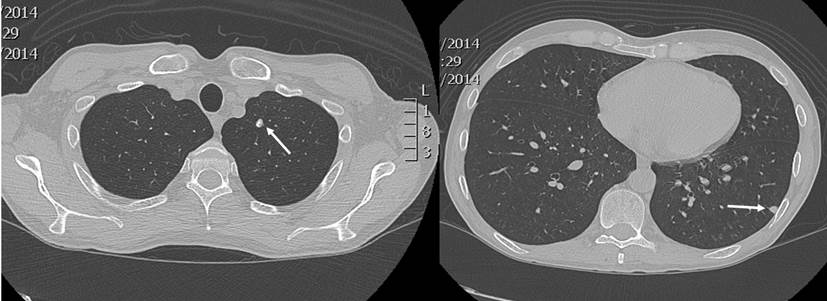

En un nuevo control endoscópico, se encontró pancolitis ulcerativa y pseudopólipos, que en comparación con la colonoscopia previa, evidenció una progresión de la enfermedad, por lo que se contempló el inicio de una terapia biológica. Se solicitaron pruebas de tuberculina (Purified protein derivative, PPD), serología para hepatitis A, B, C y una prueba de VIH. Se realizó además una radiografía de tórax, en la que se observó la presencia de un nódulo en el lóbulo superior izquierdo y otro en el lóbulo inferior, de 6 mm cada uno (Figura 1). La tomografía computadorizada de tórax confirmó dichos hallazgos (Figura 2).

Figura 1 En la radiografía de tórax se observan opacidades nodulares con densidad de tejidos blandos, proyectadas a nivel de los lóbulos superior e inferior izquierdo. Fuente: archivo de los autores.

Figura 2 Se observa un nódulo pulmonar con calcificaciones gruesas en el segmento apicoposterior del lóbulo superior izquierdo, de 6 mm de diámetro, y otra imagen nodular subpleural de 6 mm de diámetro, en el segmento superior del lóbulo inferior izquierdo, con densidad de tejidos blandos. Fuente: archivo de los autores.

Nuestro paciente no presentó síntomas relacionados con la criptococosis. Por tanto, el diagnóstico fue incidental, a partir del hallazgo inicial de nódulos pulmonares que se confirmaron mediante tomografía. Esta técnica forma parte de los métodos diagnósticos y en ella, usualmente, se observan pocos o múltiples nódulos subpleurales o masas con o sin halo. Además, en un menor número de casos, pueden apreciarse consolidaciones, derrames pleurales o un aumento del tamaño de los ganglios mediastínicos 10,11.